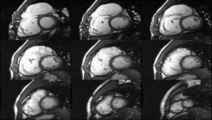

![]() An example of CMR movies in different orientations of a cardiac tumor - in this case, an atrial myxoma.[1] | |